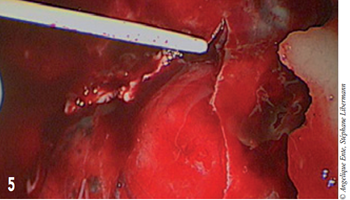

La reconstruction anatomique étant impossible, le fragment retiré est conservé, il servira d’empreinte pour mouler la prothèse de polyméthylemétacrylate (PMM). Un hématome sous dural est aspiré après ponction et incision de la dure-mère à la lame de bistouri n°11 (figure 5).

Figure 5 – Aspiration de l’hématome sous-dural.